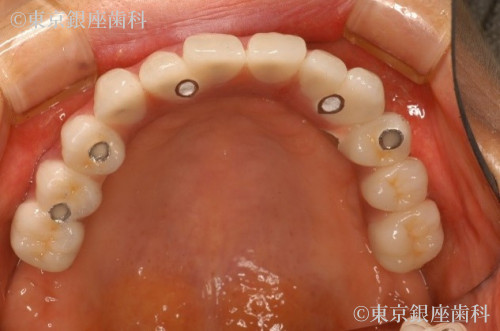

複数の奥歯を長期間失い、前歯に過度な咀嚼力の負担がかかってしまったため、全顎的にインプラントを支台とした口腔機能回復が必要となった症例

上顎に関しては上記の理由により最小本数のインプラントを支台とした全顎的な人口歯によって口腔機能の回復を予定しました。

今回の症例に関しては、上顎は全顎的な口腔機能の回復が必要で、右側の奥歯は骨の吸収が大きかったためサイナスリフトを並行して行いました。